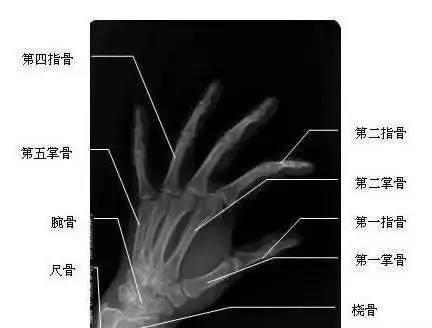

我們先來看一下雙手漂亮的“骨感”圖,這是雙手主要骨頭組成部分。骨頭外面覆蓋了肌肉、血管、神經、筋膜、皮膚等組織。腱鞘,就是指纖維鞘+指滑膜鞘的雙層套管樣結構,對肌肉的肌腱起約束、支持和滑車等作用。所謂腱鞘炎,就是指肌腱及其周圍覆蓋組織發(fā)生炎癥。腱鞘炎最常發(fā)生于手部或腕部,但也可發(fā)生于身體其他部位,如踝部。